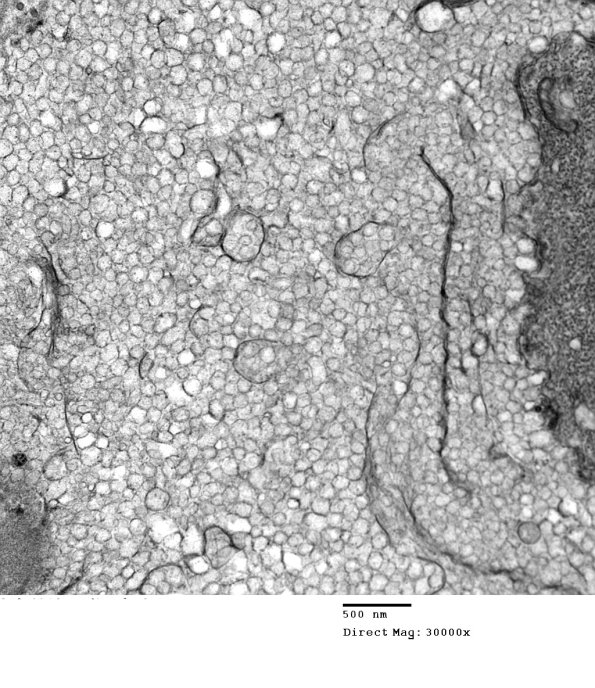

The axon in the center of this abnormal myelin collection is more dense than expected but surrounded by myelin vesicles of multiple sizes. (electron micrograph)